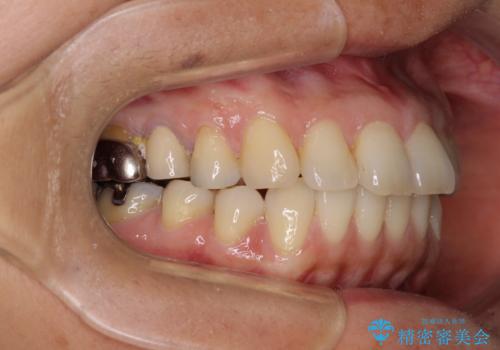

左下奥歯は、前医より難治性なので抜歯も考えるよう言われたそうですが、一度もラバーダムを用いた根管治療はされていないとのことでした。

まずは左下奥歯の根管治療を行い、痛みが引いたことを確認してから矯正治療を開始しました。

矯正治療後には、左下奥歯の症状がないことを確認し、セラミッククラウンにて補綴治療を行うこととしました。

根管治療を行う上で、ラバーダム防湿は処置の中で最も重要な要素です。

矯正治療後のレントゲン写真では、根尖部に認められた病変(骨の溶けていた像)は消失していることが分かりました。